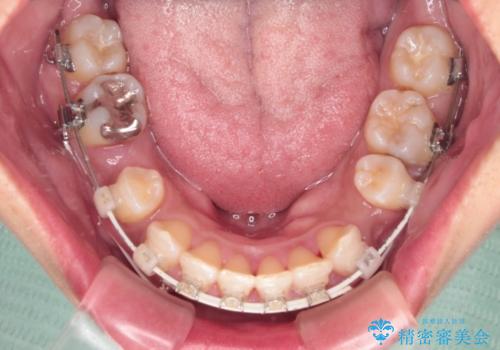

- 矯正装置

- 審美装置

「矯正装置が目立つのは避けたい」というご希望があったため、プラスチックブラケット+コーティングワイヤーを使用した審美装置を選択しました。